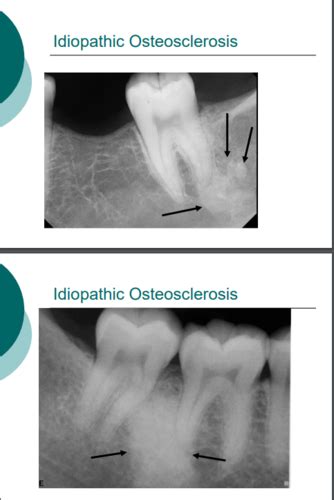

Now, you might be wondering, “How do I know if I have osteosclerosis ?” The tricky part, guys, is that osteosclerosis itself often doesn’t present with a lot of obvious symptoms, especially in its early stages or when it’s mild. Many cases are actually discovered incidentally, meaning they’re found by chance when a doctor is looking at an X-ray or CT scan for something else entirely. That’s why understanding the potential signs is so important, even if they’re subtle. In some instances, individuals might experience bone pain or tenderness in the affected areas. This pain can be dull and aching, or it can be sharp and localized, especially if the increased density is putting pressure on nerves or causing stress on the bone structure. Fractures are another significant concern. Paradoxically, even though the bones are denser, they can sometimes become more brittle and susceptible to breaking, especially with minor trauma. This is particularly true if the underlying cause affects the overall quality and structure of the bone, not just its density. Think about it: a super-hard but brittle material might shatter more easily than a slightly less dense but more flexible one. In more severe or widespread cases, especially those related to genetic conditions like osteopetrosis, you might see deformities of the bone or skeletal abnormalities. This could affect the shape of the limbs, the skull, or the spine. Other symptoms can be linked to the underlying cause of the osteosclerosis. For example, if it’s due to a bone marrow disorder, you might have symptoms related to blood cell counts. If it’s related to an infection, you’d likely have signs of infection like fever and swelling. Neurological problems can also arise, particularly if the increased bone density is pressing on nerves. This is more common in areas like the skull or spine, where the space for nerves is limited. So, how do doctors actually diagnose osteosclerosis? It almost always starts with medical imaging . X-rays are the most common tool, where osteosclerosis appears as areas of increased white density. CT scans can provide more detailed images of the bone structure, and MRI might be used to assess surrounding soft tissues or look for inflammation. Blood tests are often ordered to check for markers of bone metabolism, infections, or underlying systemic diseases that could be contributing to the condition. Bone biopsy , where a small sample of bone tissue is taken and examined under a microscope, is sometimes performed to get a definitive diagnosis, especially if the cause is unclear or to assess the bone’s quality. Your doctor will also take a detailed medical history and perform a physical examination to gather as much information as possible. They’ll ask about any pain, past injuries, family history of bone conditions, and other symptoms you might be experiencing. Putting all these pieces of the puzzle together helps the medical team determine if osteosclerosis is present and, more importantly, what’s causing it so they can figure out the best course of action for you.